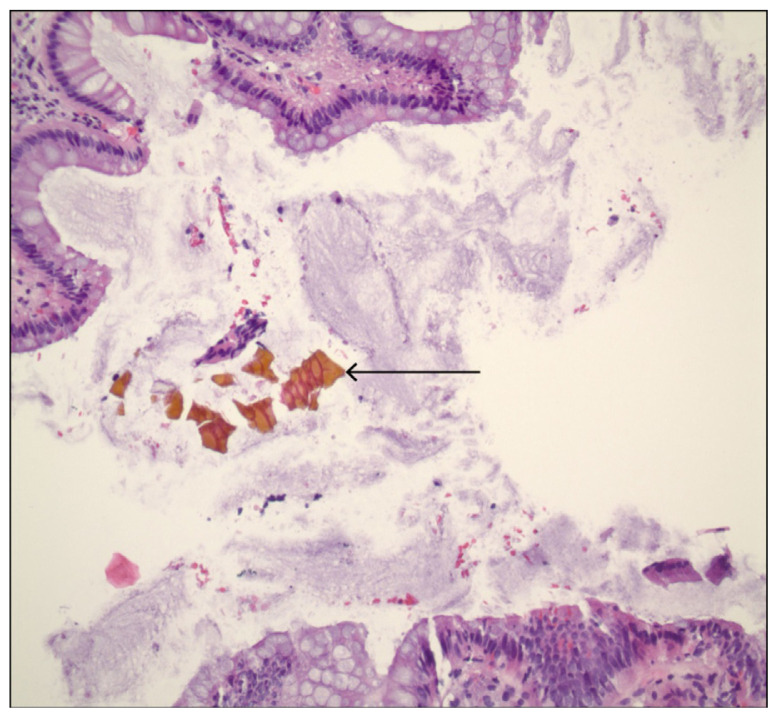

Sevelamer是一种不可吸收的聚合物,用于治疗接受血液透析的终末期肾病(ESRD)患者的高磷血症。sevelamer晶体在胃肠道(GI)中的沉积,特别是在结肠中的沉积,可引起粘膜炎症、假性息肉、溃疡、缺血或坏死。由于其罕见性和缺乏医生的认识,sevelmer诱导的胃肠道粘膜损伤(SIGMI)的实际发病率和流行率仍然未知。目前的证据是回顾性的,以观察性研究的形式。本系统的病例报告综述提供了SIGMI的概况,重点是其病因、体征和症状、发病机制、诊断和管理。检索了PubMed、Embase和谷歌Scholar等电子数据库,检索了从成立到2023年8月发表的病例报告、病例系列和摘要。搜索产生了1239篇文章,使用研究设计、英语语言和人类受试者进行了过滤。在筛选重复和不相关的文章后,只有28篇文章被纳入最终评审。红斑狼疮和腹痛是最常见的主诉。所有患者停用Sevelamer, 27例(75%)患者临床改善或症状缓解。8例(22%)患者因结肠穿孔、恶性梗阻或广泛坏死需要结肠切除术。SIGMI是在接受血液透析的患者中使用sevelamer的独特并发症。及时诊断和治疗对于预防危及生命的并发症至关重要。

Sevelamer is a non-absorbable polymer used to treat hyperphosphatemia in individuals with end-stage renal disease (ESRD) undergoing hemodialysis. The deposition of sevelamer crystals in the gastrointestinal (GI) tract, especially in the colon, can cause mucosal inflammation, pseudopolyps, ulceration, ischemia, or necrosis. Owing to its rarity and lack of physician awareness, the actual incidence and prevalence of sevelamer-induced gastrointestinal mucosal injury (SIGMI) remain unknown. The current evidence is retrospective, in the form of observational studies. This systematic review of case reports provides an overview of SIGMI, with a focus on its etiology, signs and symptoms, pathogenesis, diagnosis, and management. Electronic databases, including PubMed, Embase, and Google Scholar, were searched for published case reports, case series, and abstracts from inception to August 2023. The search yielded 1239 articles that were filtered using the study design, English language, and human subjects. After screening for duplicates and irrelevant articles, only 28 articles were included in the final review. Melena and abdominal pain were the most common complaints. Sevelamer was discontinued in all patients, and 27 (75%) experienced clinical improvement or symptom resolution. Eight patients (22%) required colectomy due to colonic perforation, malignant obstruction, or extensive necrosis. SIGMI is a unique complication of sevelamer use in patients undergoing hemodialysis. Prompt diagnosis and management are crucial to prevent life-threatening complications.